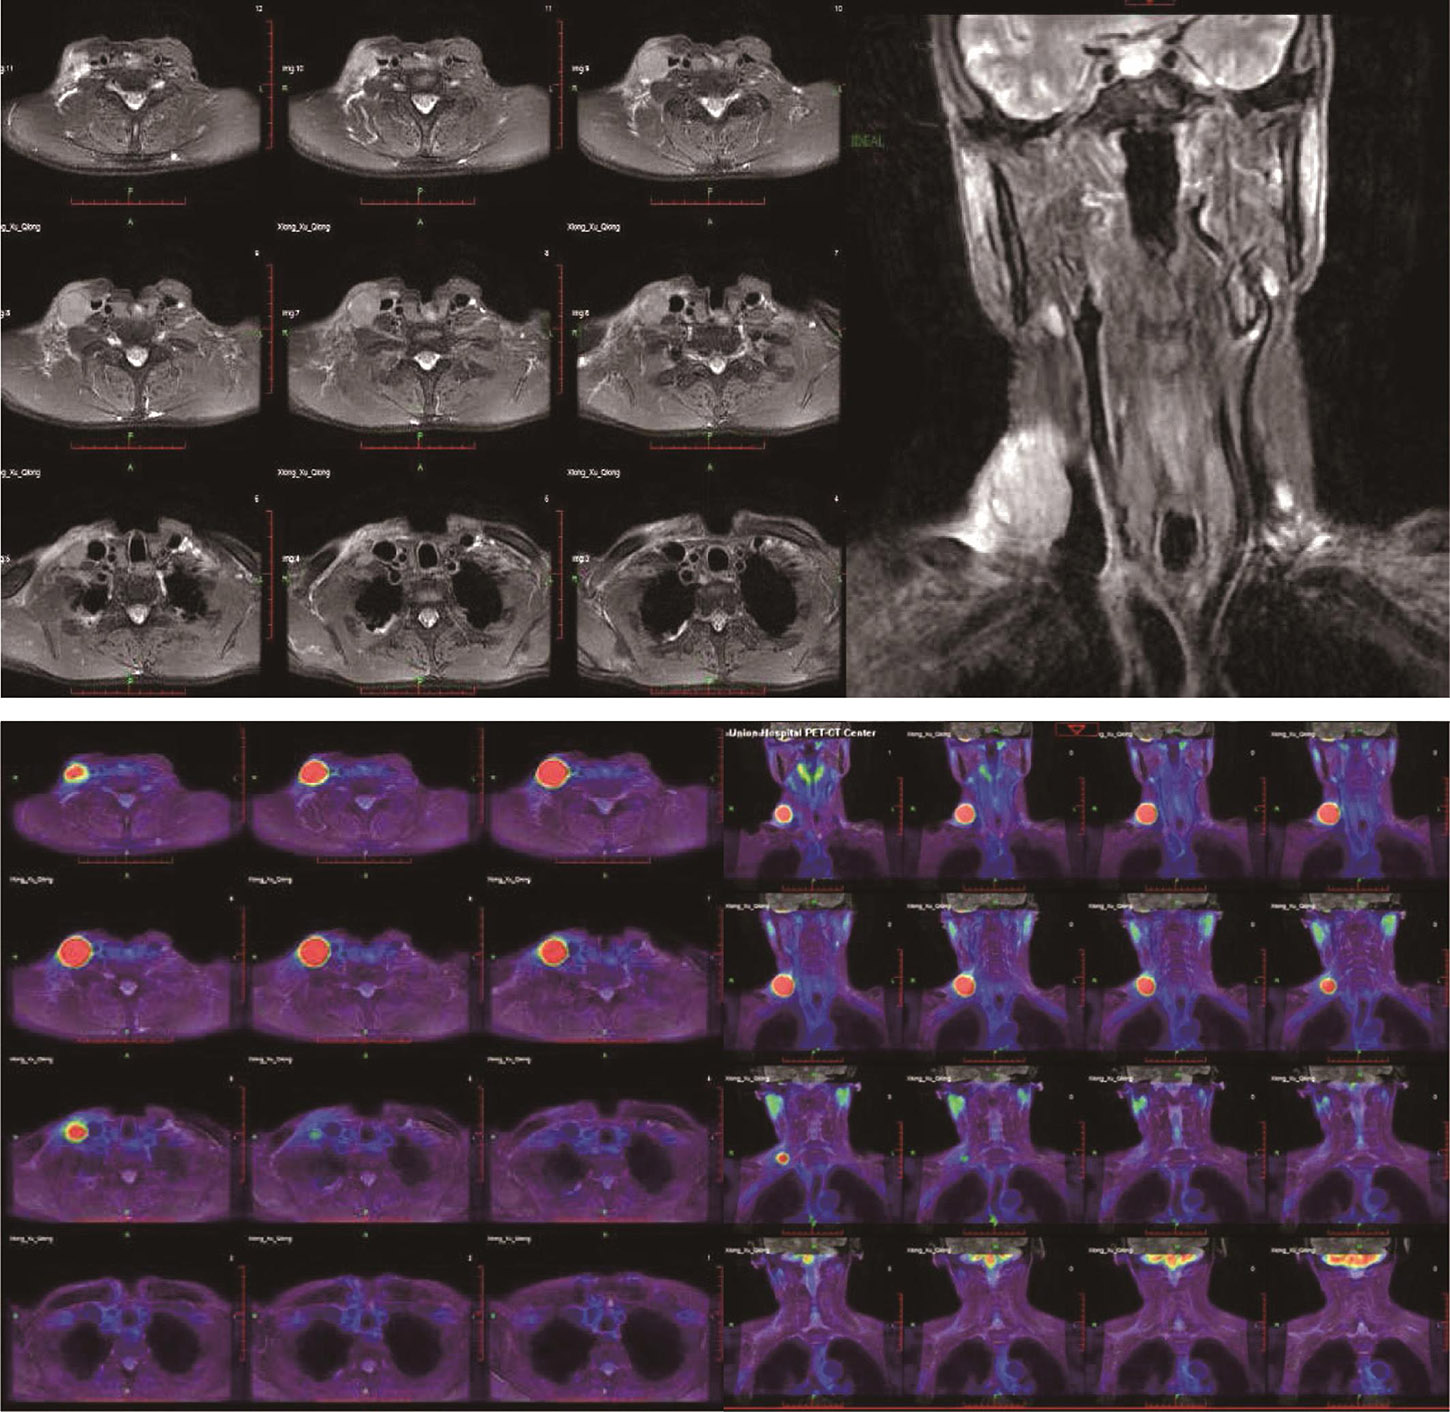

2018-11-06行全身PET-MRI:右侧下颈部及锁骨上区肿大淋巴结,代谢增高,考虑为恶性肿瘤,其他部位未见明显肿瘤转移征象(图1)。

图1 全身PET-MRI